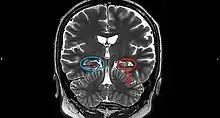

On a MRI T2-weighted or T2–fluid‐attenuated inversion recovery (FLAIR) scan, hippocampal sclerosis appears as an increased signal, smaller sized (atrophic) hippocampus with a less well-defined internal structure.[2] Increased signal means that hippocampal sclerosis will appear brighter on the MRI image. Less well-defined internal structure means the expected sharp boundaries between hippocampal gray and white matter structures are absent.[2] The total volume of the hippocampus is also reduced.[2] The reduced volume arises from neuronal cell loss, and increased signal arises from gliosis.[2]